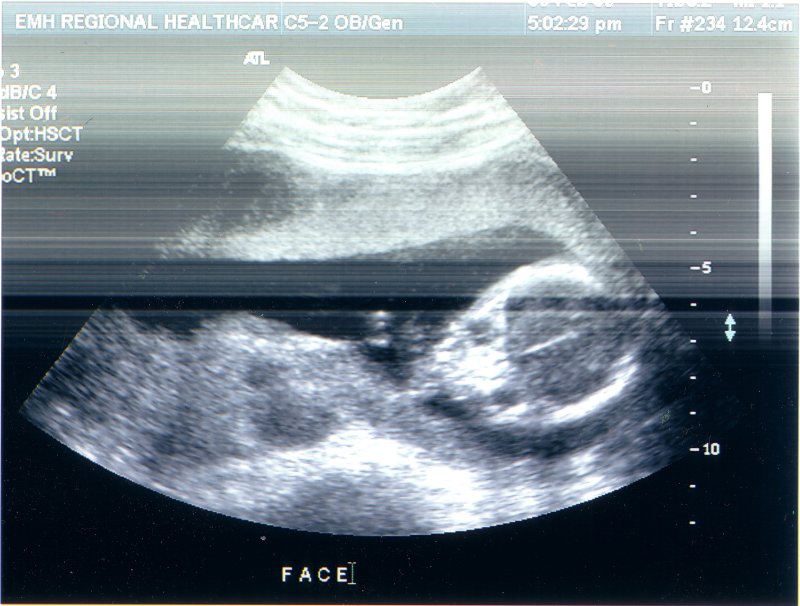

Here's Benny at 5 months. He wouldn't turn around for the technician no matter how much she tickled him. He got mad and kicked at the spots she tickled him at though. Silly sleepy boy!

March 25th, 2003